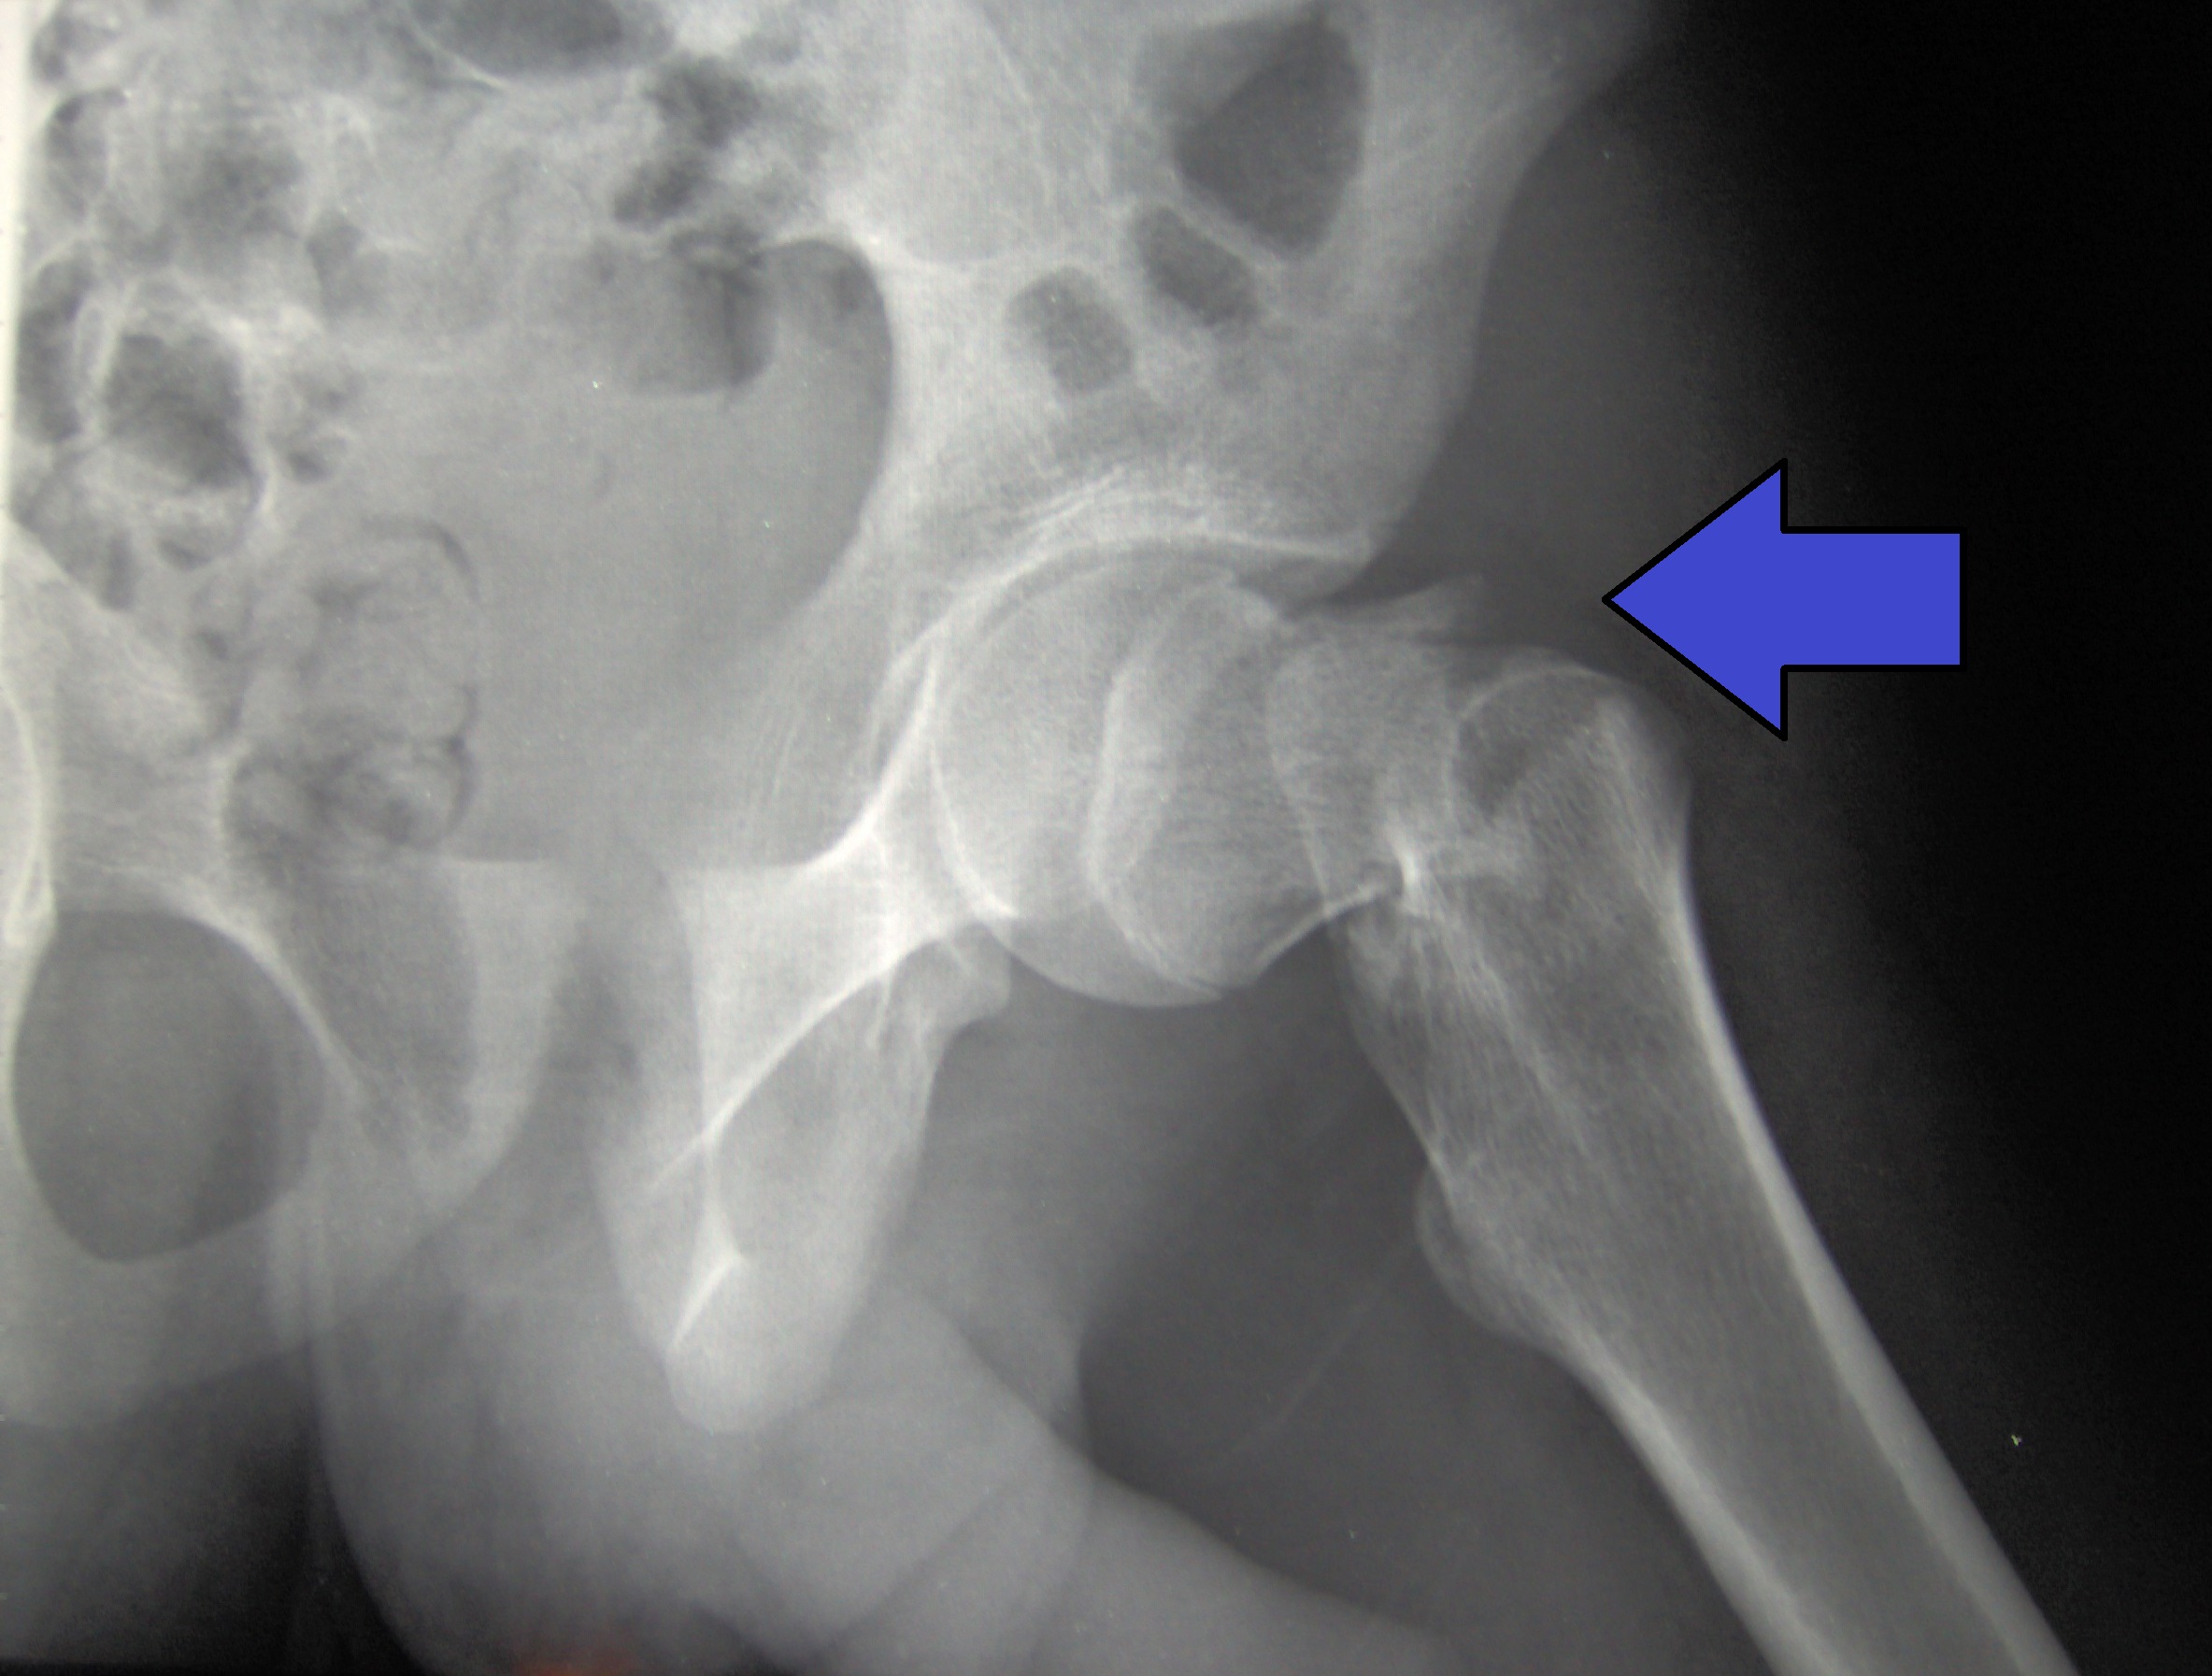

Dolor luego de la anestesia general o espinal para la cirugía de fractura de cadera

El dolor intenso es común después de una fractura de cadera. La anestesia espinal se asoció con más dolor en las primeras 24 horas después de la cirugía y más uso de analgésicos recetados a los 60 días en comparación con la anestesia general. Annals of Internal Medicine, 14 de junio de 2022.